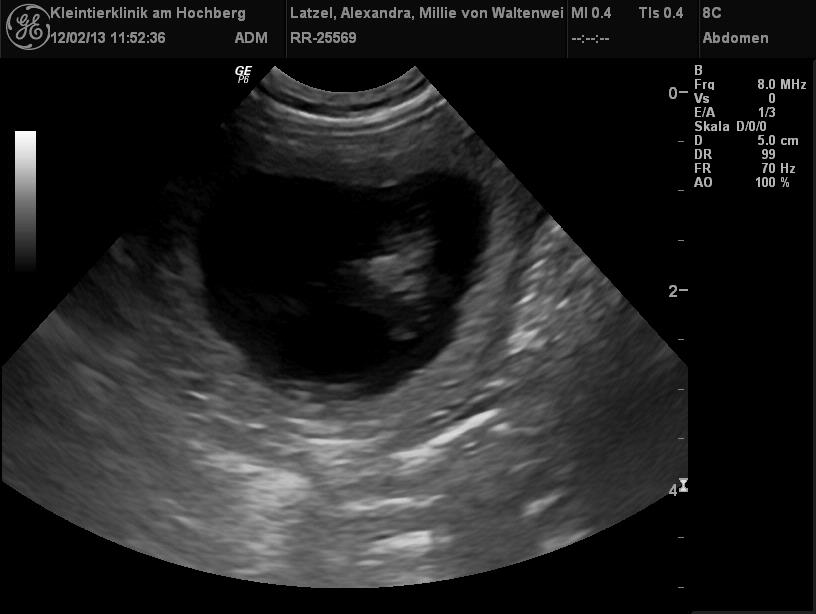

| Juhu! Millie ist schwanger! Die Ultraschallbilder beweisen es! |

Wir waren mit Millie am 12.und 13.01.2013 bei Cosmo (Edge of Eternity von der kleinen Arche) zum Decken.

Die zwei waren sich auf Anhieb sympathisch und nun erwarten wir Anfang März Welpen aus dieser Verbindung! |